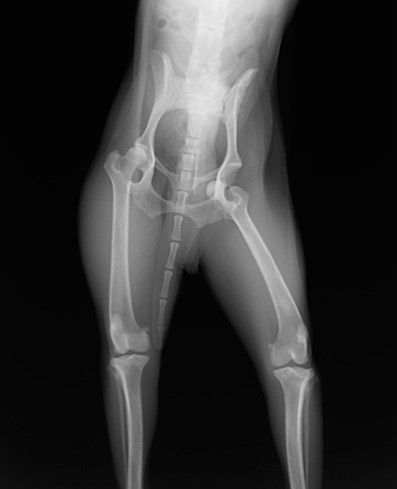

眼球摘出、眼瞼腫瘤切除、チェリーアイ整復、眼瞼縫合、瞬膜フラップ、眼球突出整復、耳介切除、垂直耳道切除、総耳道切除、鼻鏡切除、口腔腫瘍切除(上顎骨切除、下顎骨切除を含む)、各種抜歯(猫の全臼歯抜歯含む)舌腫瘍切除、唾液腺嚢胞切除、皮膚腫瘤切除、断脚(前肢、後肢、片側骨盤切除)、断尾、肺葉切除、胸腺腫切除、心膜切除、横隔膜ヘルニア整復、肝臓腫瘍切除、胆嚢摘出、胃切開、胃拡張胃捻転症候群整復、胃腫瘍切除、腸管切開、腸管腫瘍切除、直腸腫瘍切除(粘膜、全層プルスルーなど)、腎臓摘出、SUB設置手術、脾臓摘出、副腎摘出、膀胱切開、膀胱腫瘍切除(部分切除、全摘出、膀胱尿道一括切除など)、卵巣腫瘍切除、精巣腫瘍切除、卵巣子宮全摘出、肛門嚢切除、各種骨折、膝蓋骨脱臼整復、股関節脱臼整復、大腿骨頭切除、椎間板ヘルニア(各種椎弓切除術)、各種リンパ節切除 など